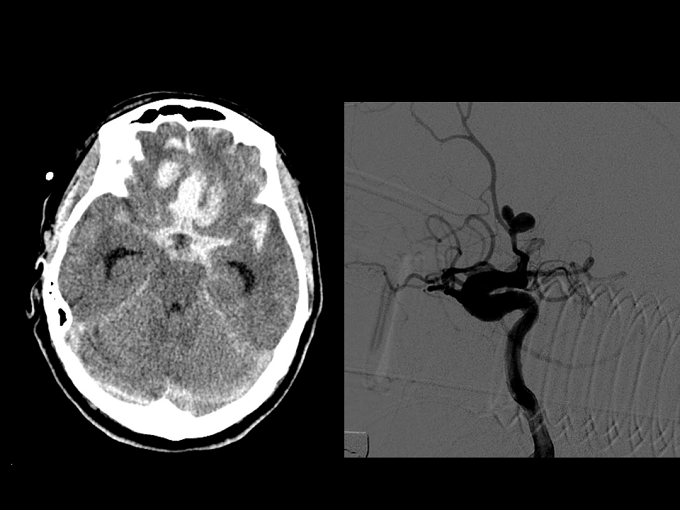

Trầm cảm,đột quỵ, suy thoái võng mạc, mất thị lực, mù vĩnh viễn, đột quỵ não…là những bệnh lý nguy hiểm có thể gặp từ diễn tiến của chứng bệnh đau nửa đầu. Tuy nhiên theo các bác sỹ, bệnh đau nửa đầu thườngđang bị các bệnh nhân nhầm lẫn với các chứng bệnh khác nên còn chủ quan trong việc điều trị.

Những người trong độ tuổi từ 20-45 là nhóm dễ mắc bệnh đau nửa đầu nhất. Phụ nữ chiếm đến 3/4 số người mắc. Đau nửa đầu ngoài ảnh hưởng nghiêm trọng đến chất lượng sống của người bệnh còn có thể dễ dẫn đến những bệnh lý nguy hiểm khác như: trầm cảm,đột quỵ, suy thoái võng mạc, mất thị lực, mù vĩnh viễn và nặng nhất là đột quỵ não,...Theo Tổ chức y tế Thế giới WHO, chứng đau đầu Migraine đang là một trong 20 nguyên nhân hàng đầu gây thương tật cho con người.

Bệnh đau nửa đầu đa số xuất phát từ các nguyên nhân liên quan đến bệnh lý mạch máu não. Và các nghiên cứu gần đây chỉ ra, gốc tự do là một trong những tác nhân nguy hiểm. Tại não, gốc tự do sinh ra liên tục, lắng đọng ở thành mạch máu, thúc đẩy quá trình xơ vữa, làm hẹp lòng động mạch khiến máu dẫn oxy về nuôi não trở nên khó khăn. Bên cạnh đó, gốc tự do và các hóa chất trung gian sinh ra trong quá trình chuyển hóa ở não làm gia tăng hoạt động bạch cầu, khởi phát quá trình viêm và sản sinh chất gây giãn mạch làm tổn thương nội mạc mạch máu, gây nên những cơn đau nửa đầu.